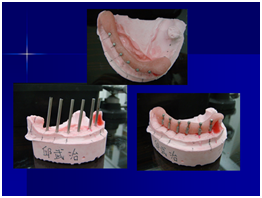

於100/06/07重新放置兩顆植體

並於100/10/25將中間兩顆植體做二階接出

由於前後植體的高低差距太大,決定將中間兩顆高度較為一致的植體假牙做連結,但前後兩顆做單顆假牙的設計。

100/11/21 補綴完成